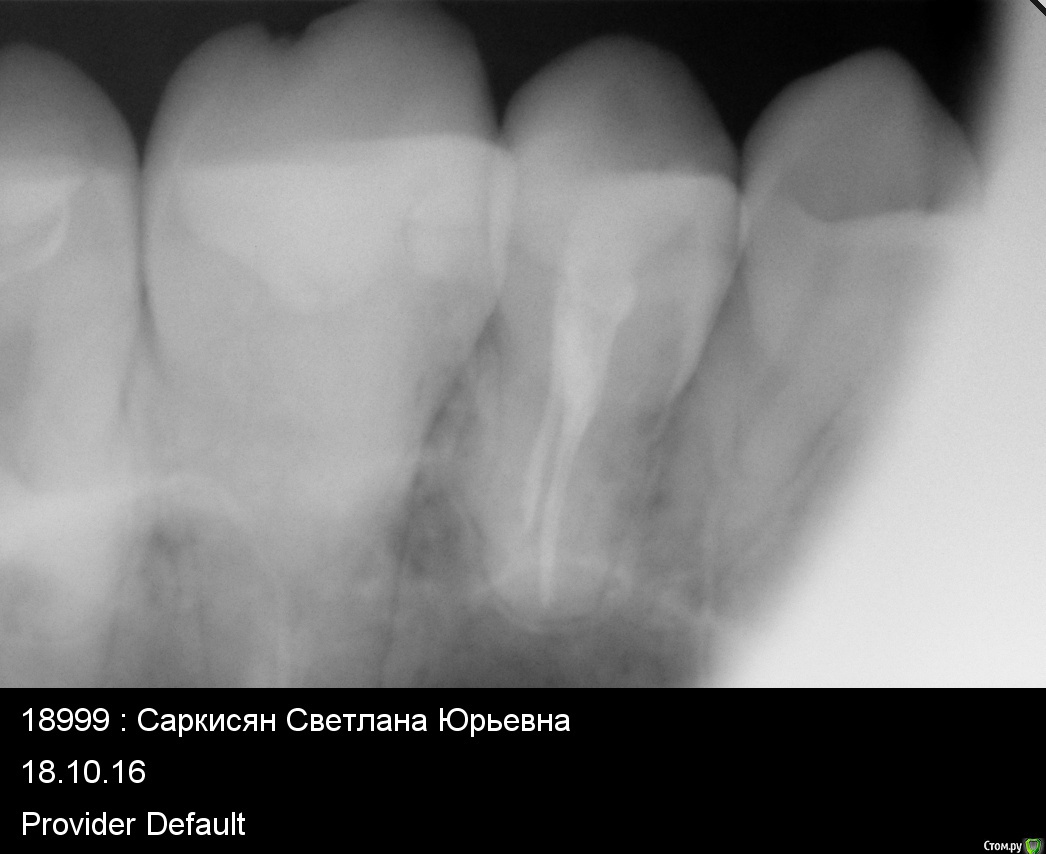

Setasy Опубликовано 14 декабря, 2016 Поделиться Опубликовано 14 декабря, 2016 (изменено) Здравствуйте! Очень нужен совет. В июле мне пролечили глубокий кариес 6-ки сверху слева. Примерно в то же время лечили и 6-ку снизу, там никак не могли подобрать нормально пломбу, больно было на ней жевать, пока не поставили ветример. Таким образом, я не могла полноценно кушать на левой стороне и проверить, все ли в порядке с верхним 6 зубом. Когда наконец смогла это делать, стала ощущать постоянный дискомфорт при жевании твердой пищи ближе к 5 зубу. Обратилась к другому доктору, он снял пломбу, думали, может что-то проседает там, ничего не изменилось. Когда он снял в следующий раз всю реставрацию, сказал, что видит там трещину корня, но не был уверен. У меня в тот же день начался острый пульпит, сильнейшая боль. Каналы мне врач пролечил, с коффердамом, с бинокулярами, все как положено, заложил кальций. Но есть на зубе по-прежнему невозможно было. Так не болит, но даже минимальная нагрузка (мягкой пищей) и все, чувствуется языком снова боль, неприятно дотрагиваться. Врач от меня отказался, говорит, что все правильно делает и не знает, почему у меня не проходит. Наверное все-таки трещина, тогда любое лечение несостоятельно. Обратилась еще к одному врачу, она рассверлила временную пломбу, промыла хлоргексидином каналы и заложила какую-то йодовую пасту. Трещины не увидела. После этого вообще до зуба не дотронуться было, все вокруг было очень болезненно и как будто камней наложили. На 4 день это острое состояние прошло и вернулось все то же, что и было. До зуба больно дотрагиваться языком и невозможно есть. Сегодня мне сделали КТ. Врач, смотревший КТ, сказал, что трещины корня не видит (хотя я прочла, что трещину корня по КТ вообще нельзя увидеть). Якобы надо расширять каналы. Что имелось ввиду, непонятно. Каналы мне точно лечили хорошо (4 штуки нашли). КТ прилагаю https://yadi.sk/d/_2x90byG33Wtt8 Снимки есть до лечения каналов. Прикладываю...и также ортопонарама. Я планирую беременность и мне хочется как можно быстрее разобраться с этим зубом. Можно ли оставить пока так как есть (допустим, если там трещина все-таки) или необходимо удаление? Если удалять, возможно ли сразу поставить имплант при удалении или нужно ждать? Ну и вообще хотелось бы услышать мнение по поводу ситуации, что может быть и что делать. Спасибо!!!!!!!! Изменено 14 декабря, 2016 пользователем Setasy Ссылка на комментарий